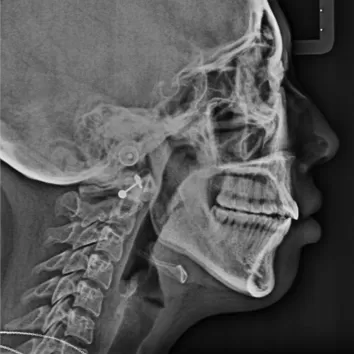

X-rays before treatment

[Panoramic Radiography/Lateral Cephalogram]